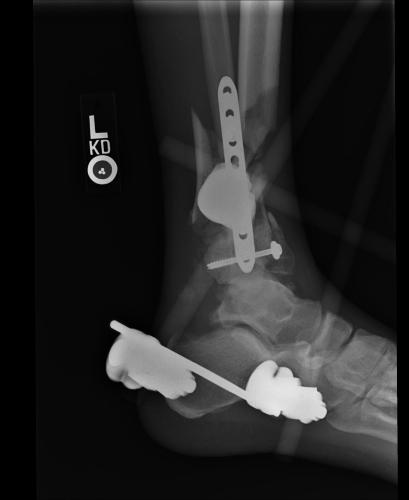

Postoperative (12th) images of left ankle

The images displayed here were created at various appointments following surgery performed by Dr. Daniel Saunders. In the X-Ray you can see

where Dr. Saunders has removed the fibula plate, joined the tibia and fibula with a screw, built-up the area of the tibia where previously

there was considerable absence of bone and lastly added the EBI OsteoGen-M Bone Stimulator (dual lead). The photos show the left side site

where the fibula plate was removed, the top site where donor bone, bone filler material and the stimulator were added and the right side

where the tissue has burst because of swelling. Liam was placed on an IV drip of Vancomycin following surgery to combat the potential onset

of Osteomyelitis. The image of the cast includes the fibula plate that was removed during surgery. The next images were taken later and show

that the staples and stitches were removed. In one of the images, you can see Liam's wife Madeline helping with leg cleanup and in one image

can be seen the EBI representative after being put to work (holding up the left leg while the latest cast cures) by Dr. Saunders. Later shots show

a healing tissue burst site with some overgrowth and Dr. Saunders cauterizing the overgrowth. Bones shifting too much (shown in X-Rays). The

last images are of the left ankle prior to the 13th surgery.